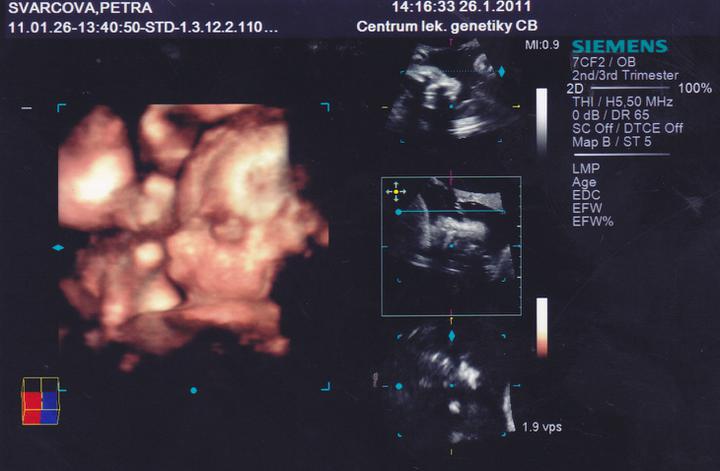

26.1.Jedu do Českých Budějovic na 4D ultrazvuk.Už se nemůžu dočkat.

Včera jsem Byla v Českých Budějovicíh.Jedno mimi váží 267g, a druhé váží 314g.A jsou to kluci.